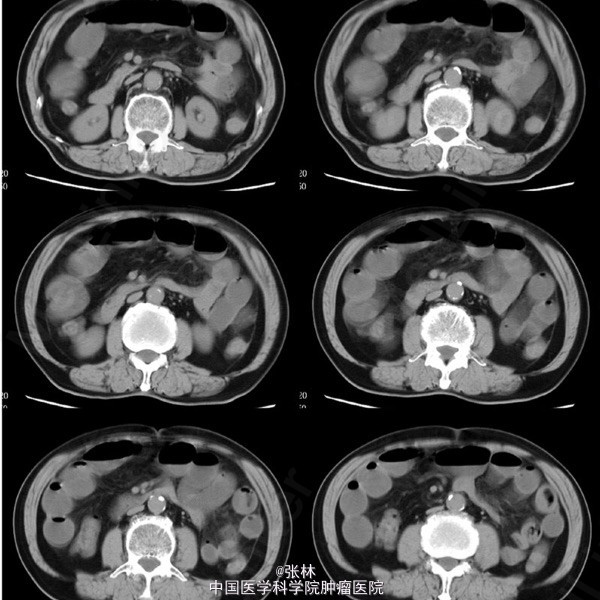

男性,72岁。 主诉:突发腹痛、腹胀伴呕吐1天。 现病史:患者1天前无诱因感全腹部疼痛,呈阵发性绞痛,无放射痛,疼痛开始不剧,伴有畏寒,呕吐胃内容物1次,量约30ml。遂到我院门诊就诊,考虑为急性胃肠炎,予抗炎、解痉护胃等支持治疗,症状未见好转,并进行性加重而入住我科。 专科检查:全腹稍胀,未见肠型及蠕动波,无上腹搏动。腹软,中下轻压痛,无反跳痛。全腹未及肿块,肠鸣音活跃,7次/分。 术中所见:探查见异物位于回肠距回盲部约50cm,大小约8*3*2cm,堵塞肠管,近端肠管充血水肿明显,肠管扩张最大处直径约8cm,未见浆膜层破裂损伤等,系膜无扭转,有少许渗液,探查全部小肠未及肿物腹腔内可见中等量黄色积液,稍浑浊,网膜及腹膜有少量脓苔。洗净腹腔内积液,于肿物边缘对肠系膜缘纵行切开约2cm,取出异物,为半个大小约8*3*2cm的冬菇。